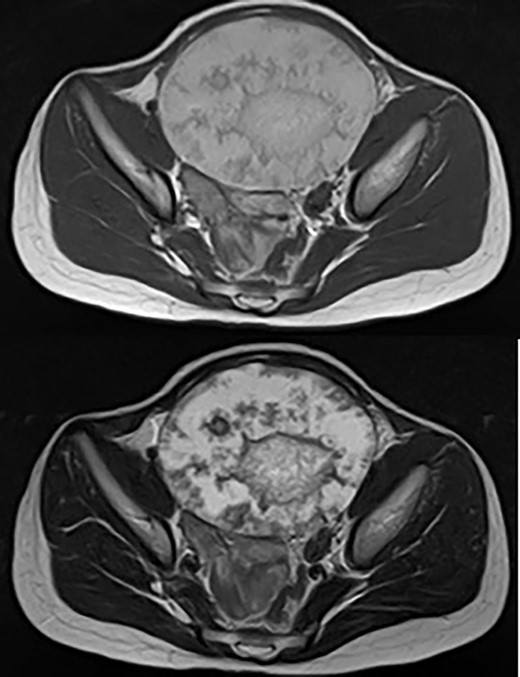

The patient was a 10-year-old girl. She visited our hospital after her grandmother noticed a mass in her lower abdomen that she had been aware of for 6 months. Abdominal ultrasonography revealed that she had a large mass centered in her lower abdomen. The tumor border was clear, the internal structure was heterogeneous and the blood flow was poor (Fig. 1). We suspected an ovarian tumor, but blood tests showed no elevated tumor markers such as AFP and CA19–9. Abdominal magnetic resonance imaging revealed a cystic mass 10 cm in diameter with high intensity on T1-weighted images and high intensity on T2-weighted images (Fig. 2). Abdominal computed tomography revealed a spleen near the navel and a cystic lesion with poor contrast that continued from the lower pole of the spleen (Fig. 3).

Abdominal magnetic resonance imaging revealed a cystic mass 10 cm in diameter with high intensity on T1-weighted images (upper) and high intensity on T2-weighted images (lower).